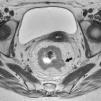

Grado de infiltración del tumorEn el diagnóstico por RM, cualquiera de las capas de la pared rectal se considera infiltrada en cualquier punto de su extensión cuando su intensidad de señal propia queda sustituida por la de la masa tumoral. Se describen varios estadios de infiltración según esta afecte a las diferentes capas del recto, mesorrecto u otras estructuras pélvicas. Un estadio T1 (fig. 2) implica la afectación de la mucosa y submucosa pero no así de la muscular, de manera que se conserva la hipointensidad de esta capa a lo largo de todo el anillo rectal, quedando la extensión del tumor por ella misma delimitada, sin ser invadida. Un estadio T2 (fig. 3) supone la afectación de la capa muscular, caso en el que su hipointensidad se pierde y se sustituye por la intensidad de señal del tumor, aunque conserva su contorno, sin infiltración en la grasa mesorrectal. Un estadio T3 (fig. 4) implica infiltración más allá de la muscular, por lo que el tumor se aprecia en la grasa como un frente redondeado o nodular3. La presencia de espiculaciones no es evidencia suficiente de infiltración3,4, ya que pueden estar causadas por fibrosis o por una inflamación peritumoral. Un estadio T4 (fig. 5) se da cuando la infiltración es de gran alcance y, rebasando la fascia mesorrectal, afecta a otras estructuras pélvicas, la hoja peritoneal (estadio T4a) o, una vez perforada esta, las vísceras intraperitoneales (estadio T4b).

Es asimismo valorable mediante RM. Independientemente de su diámetro, los ganglios afectados se muestran hipointensos o heterogéneos y con un contorno irregular, siendo estos los principales criterios para establecer un diagnóstico de infiltración positivo (fig. 6). Brown et al.5 demostraron en un importante estudio realizado en 2003 que no es recomendable considerar como criterio patológico per se el tamaño del ganglio, criterio utilizado hasta ese momento de manera general. Muchos ganglios benignos pueden ser de gran volumen, y ganglios menores de 10mm pueden contener metástasis6. En esa misma línea, Koh y MacVicar7 indican que aproximadamente el 30% de los ganglios afectados presentan tamaños por debajo de los 5mm de diámetro. Por otra parte, la hiperplasia linfoide reactiva benigna conlleva un aumento del volumen ganglionar que podría conducir a un diagnóstico erróneo7 si no se hicieran prevalecer los criterios morfológicos: hipointensidad, heterogeneidad y contorno5. El grado de infiltración ganglionar se considera según el número de nódulos afectados. De acuerdo con la clasificación TNM (tabla 1), si se localizan entre 1 y 3 ganglios afectados la infiltración se encuentra en estadio N1; si se observan más de 3 ganglios patológicos, ha alcanzado el estadio N2 (fig. 6).